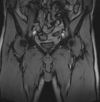

Když už máme tu okurkovou sezónu a řeší se tu všelicos, docela dost třeba právě zdravotní neduhy, které ke sportu samosebou patří, co najít mezi sebou toho největšího lazara a třeba i hypochondra? Máte jedinečnou možnost se pochlubit, co všechno vás bolí a kde máte jaký bebí. fotografická dokumentace vítána:-)